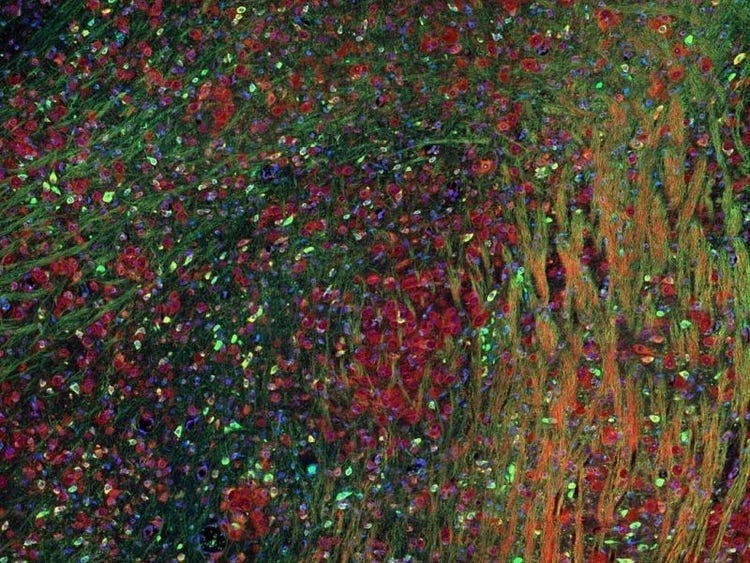

Fluorescence imaging of a mouse brain

Cette vue d’un cerveau de souris est en réalité constituée par l’assemblage d’une multitude d’images prises par imagerie de fluorescence.

Le scientifique britannique Sir George G. Stokes a d’abord constaté que la fluorine minérale devenait fluorescente lorsqu’elle était éclairée par une lumière ultraviolette, et il a inventé le mot « fluorescence ». Stokes a remarqué que la lumière fluorescente présentait des longueurs d’onde supérieures à celles de la lumière d’excitation, un phénomène aujourd’hui connu sous le nom de « déplacement de Stokes ». La microscopie de fluorescence est une excellente méthode pour étudier une matière qui peut devenir fluorescente soit sous sa forme naturelle (appelée fluorescence primaire ou autofluorescence), soit lorsqu’elle est traitée avec des produits chimiques qui peuvent devenir fluorescents (appelée fluorescence secondaire).